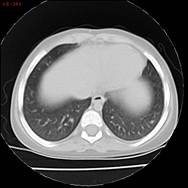

En marzo 2024, al presentar Gb: 17.000/mm3, RAE: 7.180/mm3 en monoterapia con hidroxiurea a dosis plena se decide suspender medicación para reevaluación de daño. La evaluación cardiológica es normal, mientras que la evaluación pulmonar tomográfica muestra un nuevo nódulo pulmonar en segmento basal de lóbulo superior intraparenquimatoso y una imagen inferior de 4 mm no biopsiable. Se realiza BAL, sin eosinofilia.